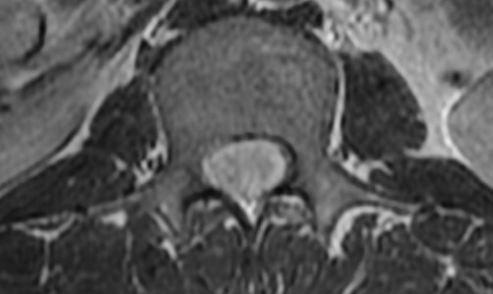

Ependymome Spinal

• Tumeur du cordon médullaire la plus fréquente de l’adulte (PED = Astrocytome Spinal)

• Centrales (originaires du canal central, contrairement à l’astrocytome qui est excentré)

• Bien délimitées, remodellantes

• Réhaussante ++

• Syryngo-hydromyélie souvent associée